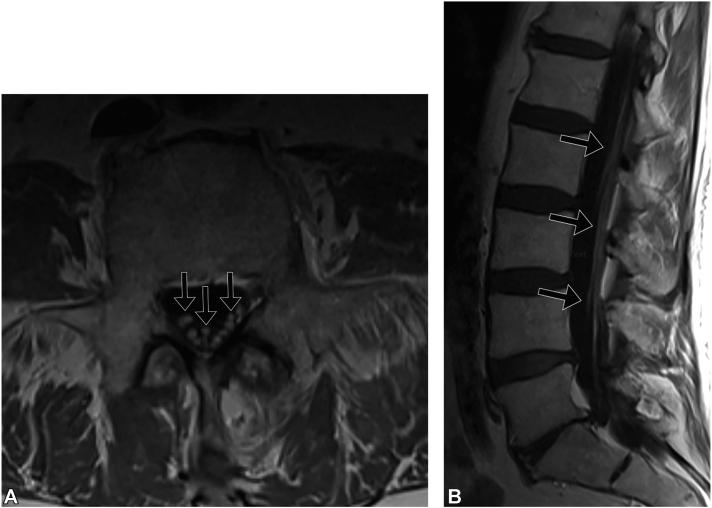

Leptomeningeal carcinomatosis from a recurrent cutaneous squamous cell carcinoma with perineural invasion in a lung transplant patient.

JAAD Case Rep. 2023 May 19;37:61-63. doi: 10.1016/j.jdcr.2023.05.014. eCollection 2023 Jul.